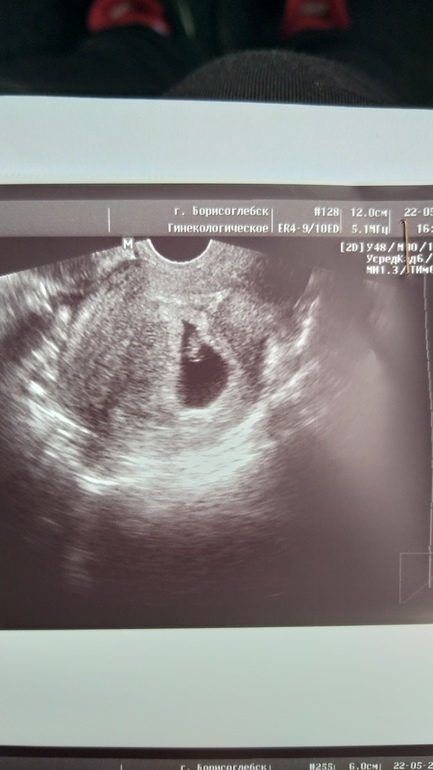

Узи 7 нед 1 день

УЗИ, КТГ, доплерДевчат, сходила я сегодня на узи. Очень обрадовалась что малышик хорошо, размер малыша 10,4 мм, сердечко 152 уд. Всё по сроку сказали. Но.... девчат меня очень огорчило вот что, может у кого такое было и чем закончилось?

Малвш очень очень низко (трое родов у меня преждевременных) ретрохориальная гематома (размер не поняла где смотреть) киста в прааом яичнике 60 мм вроде (у меня почти год болел пах тянул, по всем врачам ходила, думали аппендицит, хотели вырезать) локальный гипертонус по всей матке. Небольшая отслойка плаценты. Узистка поставила угрозу прерывания, но сказала в целом все не плохо, не пугала меня. Сказала все у врача узнаешь. К врачу в жк в понедельник. Все выходные ждать Ааааа. Девчата меня больше всего напугала отслойка. Посмотрите пожалуйста бумажки.... я и так в основном лежу и больше 1 кг не поднимаю.